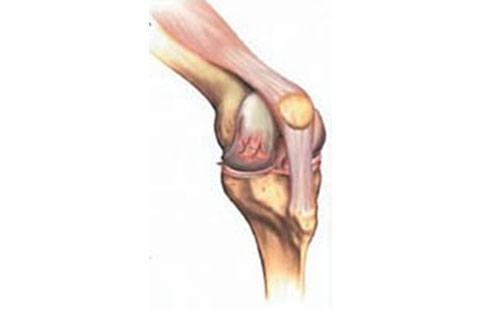

Como sintoma apresenta principalmente dor, dificuldade para movimentação da articulação e períodos de aumento de volume (derrame articular).

Na artrose ocorre desgaste da cartilagem ao longo do tempo. Com a progressão da doença ocorre exposição da superfície do osso causando dor.

Os principais sintomas da artrose são dor e sensação de rigidez na articulação (joelho).